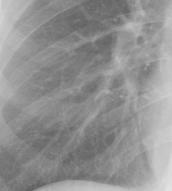

Refer to caption

(a)

(b)

(c)

(d)

Figure 8: Enhancement result on NIH ChestX-Ray14 image. One network was trained on the original X-ray and a second network was trained on the enhanced X-ray (a) Original X-ray (b) Enhanced X-ray (c) Zoom (d) Zoom -Enhanced